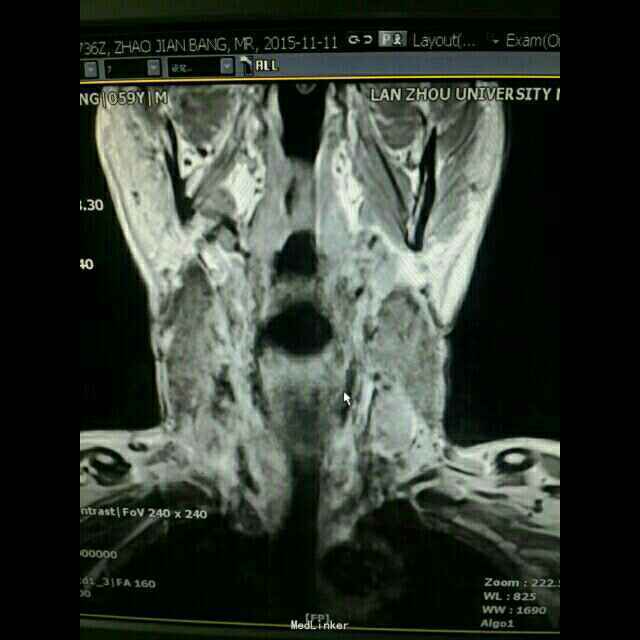

专科检查:颈部左侧胸锁乳突肌后缘中点可触及一大小约1.5×2.0cm肿物,类梭型,界清,质硬,无疼痛,活动度良好。 颈部CT及核磁检查

诊断:颈部左侧纤维瘤病。全麻下行:颈部左侧肿物切除术+神经移植术(备)。术中探查肿物与臂从神经界限清,排出神经纤维瘤可能,考虑肌肉来源肿瘤。